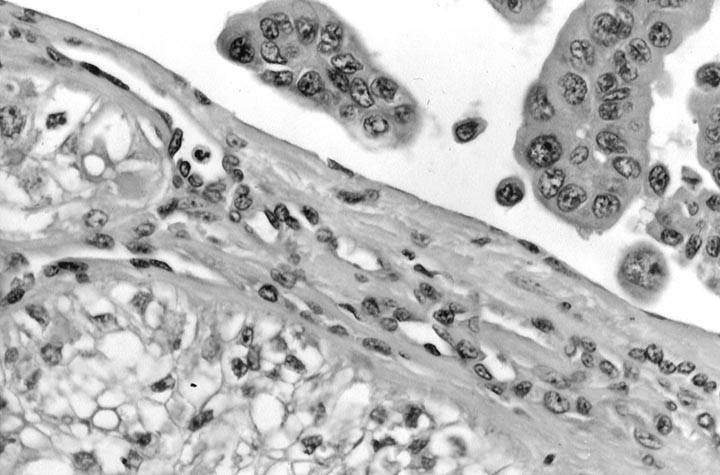

FIGURE 3

Mucoepidermoid carcinoma: A case showing concomitant tall cell variant of papillary carcinoma and mucoepidermoid carcinoma.